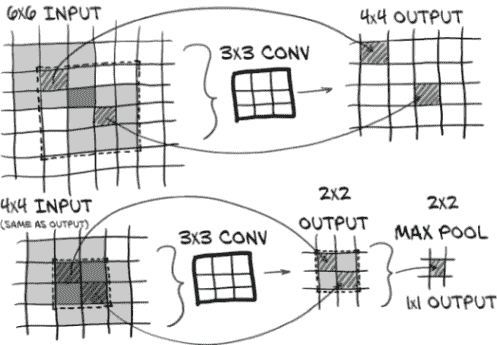

我们可以在图 11.6 中看到我们块的卷积在 2D 中表示。由于这是较大图像的一小部分,我们在这里忽略填充。(请注意,未显示 ReLU 激活函数,因为应用它不会改变图像大小。)

让我们详细了解输入体素和单个输出体素之间的信息流。当输入发生变化时,我们希望对输出如何响应有一个清晰的认识。最好回顾第八章,特别是第 8.1 至 8.3 节,以确保您对卷积的基本机制完全掌握。

图 11.6 LunaModel块的卷积架构由两个 3 × 3 卷积和一个最大池组成。最终像素具有 6 × 6 的感受野。

我们在我们的块中使用 3 × 3 × 3 卷积。单个 3 × 3 × 3 卷积具有 3 × 3 × 3 的感受野,这几乎是显而易见的。输入了 27 个体素,输出一个体素。

当我们使用两个连续的 3 × 3 × 3 卷积时,情况变得有趣。堆叠卷积层允许最终输出的体素(或像素)受到比卷积核大小所示的更远的输入的影响。如果将该输出体素作为边缘体素之一输入到另一个 3 × 3 × 3 卷积核中,则第一层的一些输入将位于第二层的输入 3 × 3 × 3 区域之外。这两个堆叠层的最终输出具有 5 × 5 × 5 的有效感受野。这意味着当两者一起考虑时,堆叠层的作用类似于具有更大尺寸的单个卷积层。

换句话说,每个 3 × 3 × 3 卷积层为感受野添加了额外的一像素边界。如果我们在图 11.6 中向后跟踪箭头,我们可以看到这一点;我们的 2 × 2 输出具有 4 × 4 的感受野,进而具有 6 × 6 的感受野。两个堆叠的 3 × 3 × 3 层比完整的 5 × 5 × 5 卷积使用更少的参数(因此计算速度更快)。

我们两个堆叠的卷积的输出被送入一个 2×2×2 的最大池,这意味着我们正在取一个 6×6×6 的有效区域,丢弃了七分之八的数据,并选择了产生最大值的一个 5×5×5 区域。现在,那些“被丢弃”的输入体素仍然有机会贡献,因为距离一个输出体素的最大池还有一个重叠的输入区域,所以它们可能以这种方式影响最终输出。

请注意,虽然我们展示了每个卷积层的感受野随着每个卷积层的缩小而缩小,但我们使用了填充卷积,它在图像周围添加了一个虚拟的一像素边框。这样做可以保持输入和输出图像的大小不变。